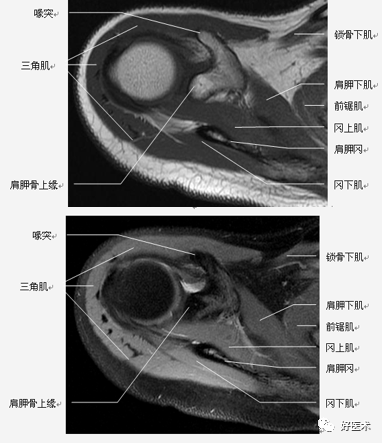

肩关节固有肌群

肩关节非固有肌群:斜方肌、背阔肌、肩胛提肌、菱形肌、前锯肌、胸大肌、胸小肌、锁骨下肌。

(2)肩袖

肩袖是由冈上肌、冈下肌、小圆肌和肩胛下肌的肌腱构成。前三个肌腱由上向下均止于肱骨大结节,而肩胛下肌腱止于肱骨小结节。

位于冈上肌腱与肩胛下肌腱之间的间隙称之为旋转间隙( rotator interval) 。其内有喙肱韧带、肱二头肌长头腱、上盂肱韧带和喙突。